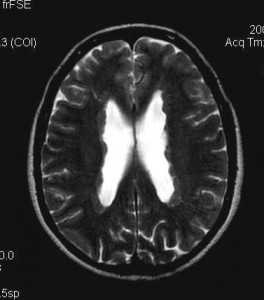

(б) MPT, FLAIR, аксиальный срез: у того же пациента определяется, что выявленное образование имеет неоднородно гиперинтенсивный сигнал. Обратите внимание на кортикальные туберсы и очаги гиперинтенсивного сигнала, расположенные в субкортикальном белом веществе. При операции была выявлена СГКА.